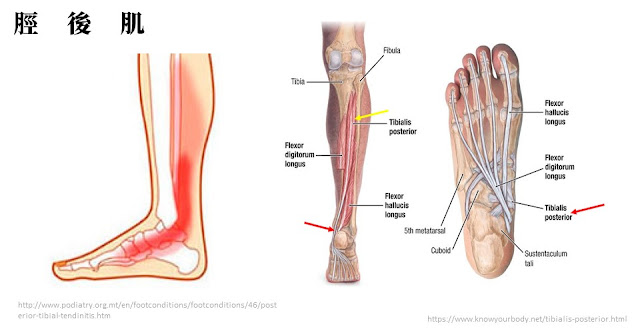

脛後肌是幫助支撐足弓重要的肌肉,而脛後肌失能是最常導致成人後天扁平足的原因,肌腱跟關節一樣,若力量不夠,用久了也可能出現退化而失去功能,當脛後肌支撐足弓的能力變差,足弓就會塌陷越來越嚴重。

另外,脛後肌的內在張力也能夠幫助維持足底的韌帶的緊度,例如:長、短蹠韌帶、彈性韌帶(spring lig.)等等,所以當脛後肌出現問題,這些幫忙維持足弓的韌帶也會跟著失去穩定度。

|

脛後肌從小腿往下連接到舟狀骨、楔狀骨及蹠骨底,若出現疼痛會發生在內踝或足弓的位置 |

脛後肌失能因為脛後肌無法支撐足弓,導致足弓塌陷、產生疼痛 |